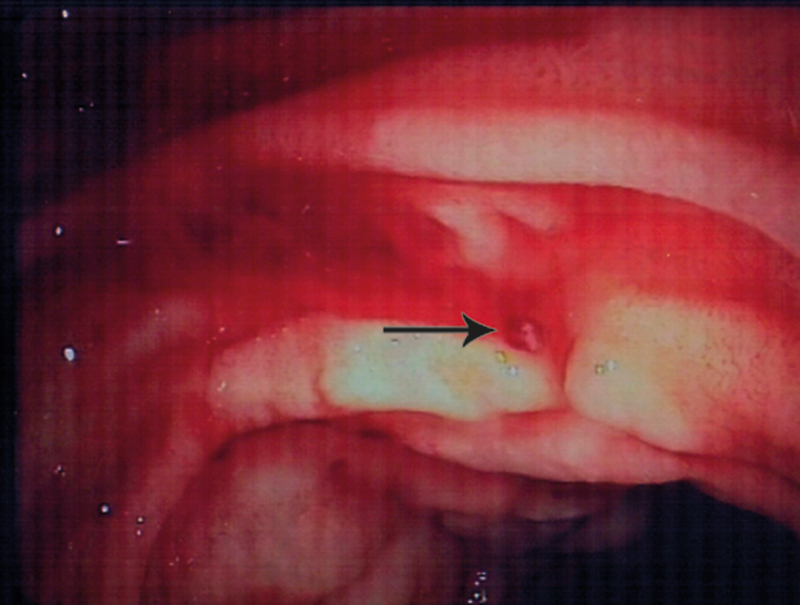

Pasienten ble gitt to nye poser med SAGMAN-blod, og man startet i tillegg behandling med traneksamsyre 1,5 g × 4 intravenøst. Ny gastroskopi på ettermiddagen samme dag viste fortsatt frisk blødning fra samme område i duodenum. Det ble igjen injisert fortynnet adrenalin, noe som resulterte i avtakende blødning. For å få bedre oversikt brukte man et ERCP-skop (optikk ut til siden). Man kunne da se sivblødning fra et punkt uten sårbunn (fig 1). Det ble injisert polidocanol 1 %, totalt 4,5 ml à 0,5 ml og deretter applisert argonplasmakoagulasjon (APC) nøyaktig mot det blødende punktet inntil full hemostase (fig 2).

Arteriell blødning fra en makroskopisk normal slimhinne ga en diagnostisk avklaring. Funnet var forenlig med Dieulafoys lesjon (exulceratio simplex), det vil si blødning fra en dilatert submukøs arteriole.